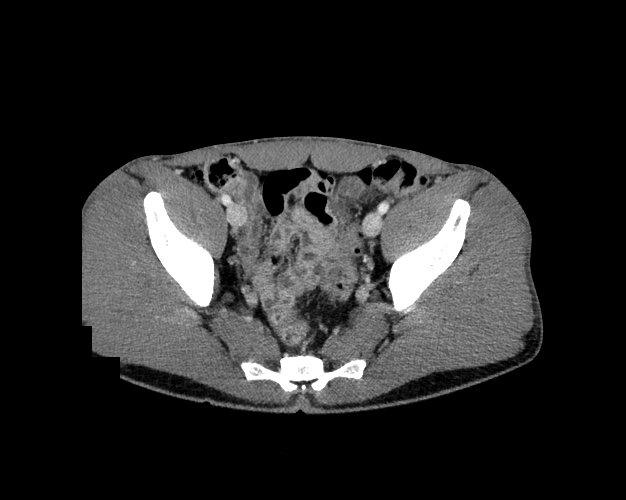

Pelvis

Covers pelvic MRI anatomy.